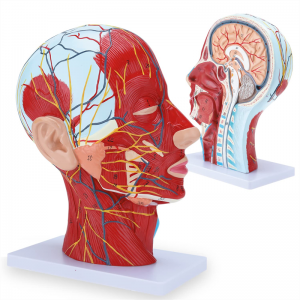

| Awọn ẹya | Awoṣe naa fihan ọrọ ayọ ti agbegbe ti apakan ti inu ati ọrun, ati awọn ẹya ara ti awọn iṣan ara ati awọn ẹya ara, ati awọn ẹya 84 wa ti o nfihan awọn ami lapapọ. |

Awọn ẹya】 o ṣafihan awọn iṣan ti o fara ara ti oju ti o farabalẹ; Awọn ohun elo ẹjẹ ti o dara julọ & awọn iṣan ti oju & scalp; Awọn ẹya inu ti Patiod erumlandi ati oke atẹgun; Eto apakan-ilẹ Sagittal artical ti ọpa ẹhin.

Awoṣe yii fihan awọn alaye ti ọrun-ọrun ati apakan sagittital ti eniyan. pẹlu superficial

awọn iṣan ti oju oju; Awọn ohun elo ẹjẹ ti o ga julọ ati awọn iṣan oju ti oju ati awọsanma; Awọn ẹya inu

ti parotid blandi ati atẹgun oke; Eto apakan-ilẹ Sagittal artical ti ọpa ẹhin.

Awoṣe ṣe afihan ọrọ-ọrọ ti agbegbe ti aarin ati awọn apakan sagittal ita ti ori ati ọrun ati awọn ẹya ara ati awọn ẹya ara ẹrọ ti ofura, pẹlu apapọ awọn olufihan oju opo wẹẹbu 100.

Awoṣe yii jẹ ori ti o tobi pupọ ati awoṣe iṣan ti o ni agbara nla ati eto aarin ti ẹṣẹ parotid ati atẹgun oke, ati apakan apakan apakan Sagitttal ti ọpa ẹhin